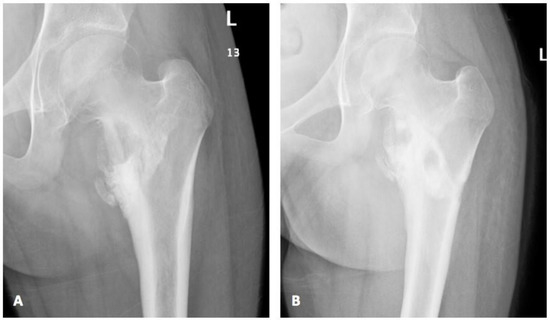

| Index case | 12Y/F | Healthy child | Chronic osteomyelitis | Tissue culture | P. species | VRC total 6 months with surgical debridement | Resolution |